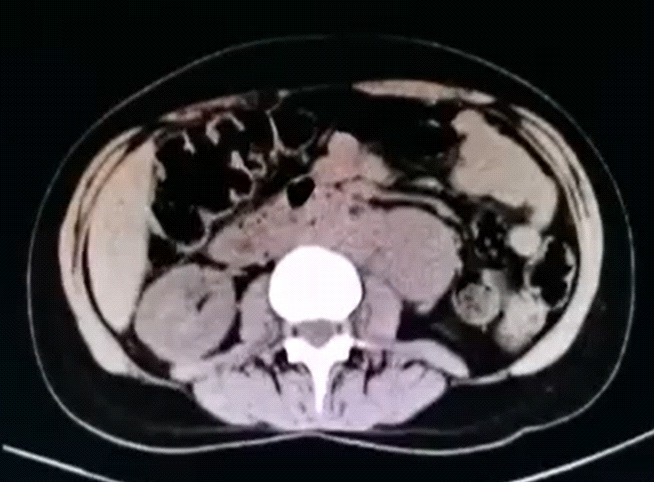

La tomografía abdominal sin contraste mostró una tumoración sólida de probable origen neoformativo en espacio pararrenal anterior izquierdo (retroperitoneo) parcialmente valorada por falta de la fase contrastada, asociada a adenopatías retroperitoneales ipsilaterales (figura 1). La resonancia magnética nuclear (RMN) mostró alteración de la señal en la medula espinal de la región cervical y dorsal de C5 a T10, luego de la administración de contraste se observa áreas de realce en esas regiones. Los cuerpos vertebrales sin evidencia de lesiones expansivas ni colapsos (figura 2). Además, la RMN encefálica evidenció lesiones desmielinizantes en la región posterior del tronco del cuerpo calloso, en la región posterior de los cíngulos a predominio izquierdo y en la región posterior al cuerno occipital del ventrículo lateral izquierdo (figura 3).

El segundo problema es el dolor abdominal, que es transitorio y probablemente debido a la misma mielitis transversa que puede caracterizarse con un dolor lancinante, inicialmente en cinturón. Esto llevó a realizar una TEM abdominal que reveló una tumoración retroperitoneal que impresionan masas ganglionares. El diagnóstico diferencial puede ser amplio e incluyen neoplasias como linfoma o sarcomas. Por la localización esta lesión de masa requerirá una biopsia laparoscópica o por radiología intervencionista.